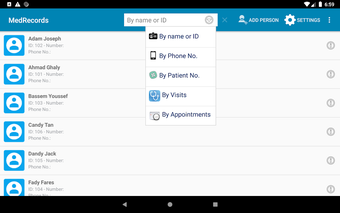

The Android Medical Records App by MedClin is a free medical records tracker app that allows users to store anamnesis, patient records, patient history, and health information. It is easy to use and provides numerous features such as username and password authentication, exporting medical data to Excel Sheet, and the ability to attach medical documents of any type. The app also has a smart search feature that allows users to search for patient information by name or ID, and even capture a photo for their profile.